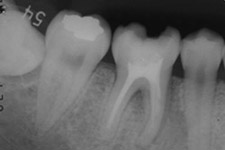

治療前のレントゲンの様子

移植直後。歯根がまだ完成していない歯では、根の先が開いていることに気づきます。